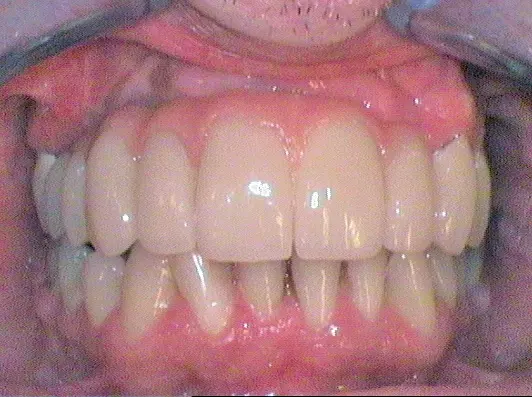

Nach Freilegung der Implantate regio 026,027 im Februar 2020, bei der auch die Implantation regio 037 (T3, Zimmer Biomet Dental, 4,0 mm x 13,0 mm) vorgenommen wurde (Abb. 32 OPG nach Freilegung), erfolgte im März nach Abformung mit offenem Löffel (open tray technique) und Gesichtsbogenregistrat die prothetische Versorgung mittels CAD/CAM gefräster Abutments (Dentaltechnik Hessel und Lutgen, Trier) und transversal verschraubter, verblockter VMK-Kronen (Abb. 33-36). Die Freilegung und Versorgung des Implantates 037 ist zusammen mit der Entfernung des Zahnes 38 für Juli 2020 geplant.